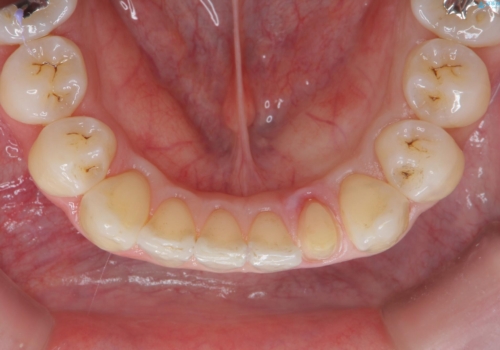

プラスチックの詰め物と比較して、変色もなく、脱離もしにくいセラミッククラウンで修復しました。

前歯のステインはエアフローという方法で綺麗にクリーニングしています。

- 16.5万円(仮歯1.1万円、セラミッククラウン(ジルコニアクラウン・スペシャル)15.4万円) エアフロー代別(1時間/1.1万円)費用は治療当時の料金となります